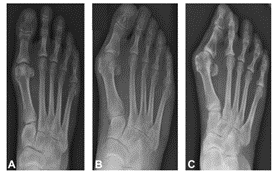

รูป x-ray แสดงภาวะนิ้วหัวแม่โป้งเท้าเก (A) นิ้วเท้าเกระดับน้อย (B) นิ้วเท้าเกระดับกลาง (C) นิ้วเท้าเกระดับมาก